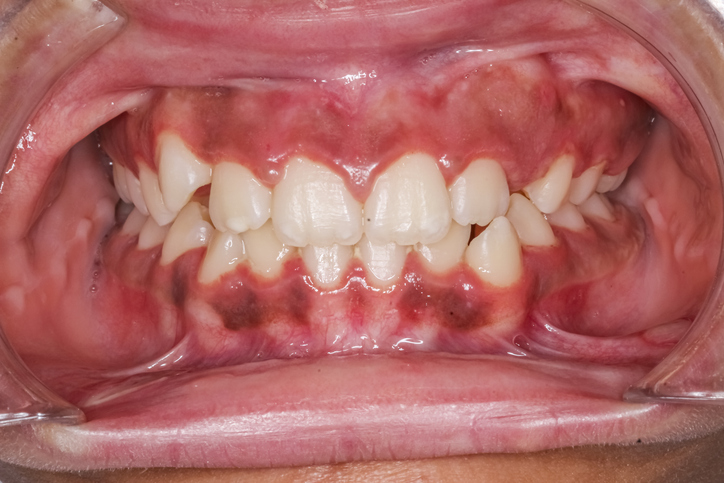

★잇몸 미백은 어두운 색(갈색 또는 검은색)으로 착색된 잇몸을 보다 밝고 건강한 분홍빛으로 되돌리는 치과 시술입니다. 이는 주로 심미적인 이유로 시행되며, 미소를 더욱 깨끗하고 건강하게 보이도록 도와줍니다.

✅ 잇몸이 어두워지는 이유

-잇몸 색이 어두워지는 원인은 다양합니다.

1. 멜라닌 색소 침착

●피부에 멜라닌이 많듯이, 잇몸에도 멜라닌이 많이 분포하면 어두운 색으로 보일 수 있습니다.

●유전적 요인이 큼니다. (특히 동양인, 흑인 등)